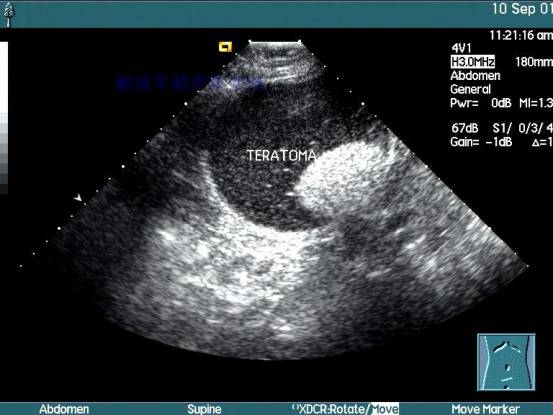

首先超声波检查是利用人体对超声波的反射进行观察。是子宫及其附件疾病和妊娠子宫判断的主要方法。